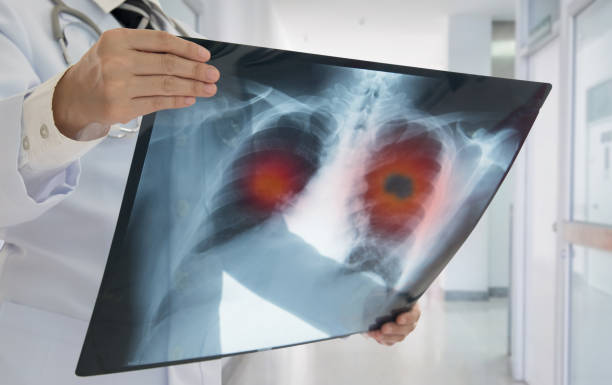

1990년대 암환자의 5년 생존율은 40%에 불과했지만 최근에는 약 70%까지 증가한 것으로 파악되며, 폐암과 같이 생존율이 낮았던 암들의 생존율도 크게 높아지고 있습니다. 생존율은 초기에 발견하여 대처하는 것이 좋기 때문에 이번 기회에 폐암 초기 증상을 알아보시고 인지하는 것이 중요합니다.

폐암 예방은 궁극적으로 폐암의 원인을 차단하는 것이며, 흡연자라면 기본적으로 금연을 해야 합니다. 아울러한 최근 여성의 폐암 발병률이 증가하고 있는데 아무래도 가스레인지를 통해 폐에 유해 물질이 들어가는 경우가 많기 때문입니다. 따라서 가족력이 있는 사람은 남녀를 가리지 말고 정기적으로 건강 검진을 받아야 하며 가족력이 없다 하더라도 주의를 기울이고 정기적인 건강 검진을 받는 것이 좋습니다.